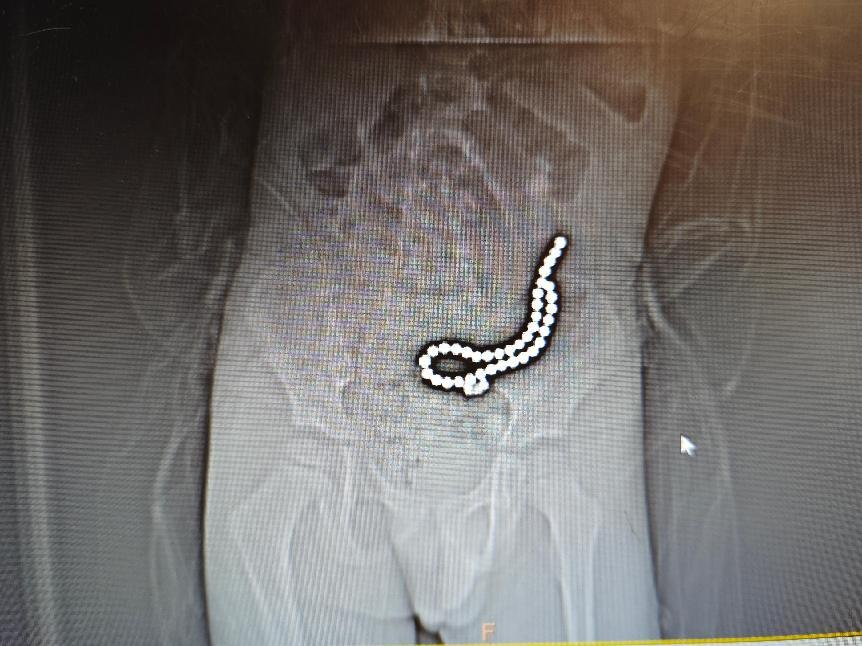

經(jīng)過初步的影像學(xué)檢查,醫(yī)療團(tuán)隊(duì)發(fā)現(xiàn):病人體內(nèi)竟然有37顆異物,連在一起呈手串狀,并伴有小腸穿孔。

術(shù)前腹部DR片